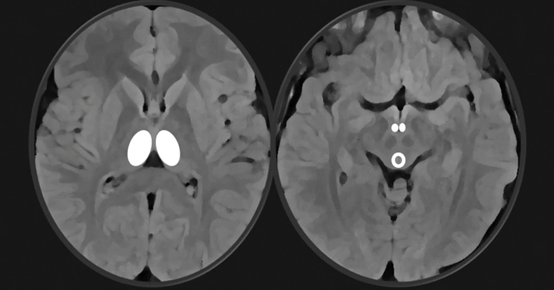

MRI

Lesions

of:

Medial

thalami

Mammillary

bodies

Periaqueductal

grey matter

T2/FLAIR,

restricted diffusion, contrast enhancement